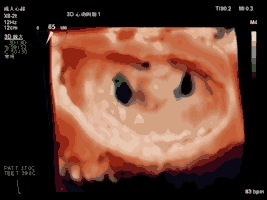

本例手术使用TrueVue实时三维双容积视野同时显示二尖瓣左房观和左室观,画面清晰,界面友好,使得手术操作“如虎添翼”,更加便捷和安全。本例手术导管操作总时间(从穿刺心尖到闭合心尖)仅为10分钟。系列图像如下:

夹合术前:三维心超示A2脱垂